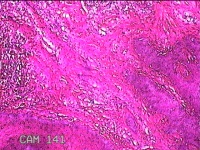

右侧头皮息肉

性别

男

年龄

46岁

临床诊断

一般病史

发现右侧头皮息肉2年余。

标本名称

大体所见

带皮肤组织2x1.2x0.8cm一块,表面光滑,切面灰白粉红色,质中。